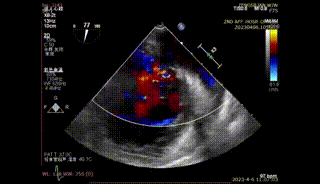

图1-4. 术前在交界、左室长轴切面及3D视角下可见大量二尖瓣反流,反流区宽,MultiVue下可见P2-P3脱垂